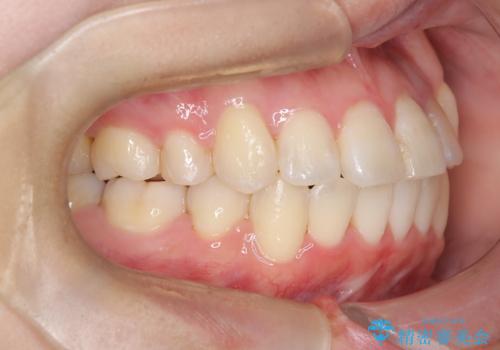

【ワイヤー矯正】八重歯 歯のでこぼこを治したい!

かなり綺麗に並ぶ事ができ大変満足していただけました。

叢生量がかなり多かったのですが、歯肉退縮も失活歯も無くとても綺麗な歯並びになりました。

歯のでこぼこは、歯周病や虫歯のリスクも、とても高いので、見た目のみならず、将来の歯の寿命自体もかなり伸ばす事が出来た治療でした。

歯の寿命を伸ばす為には、歯磨きをし易い環境を作る事がとても大切です。